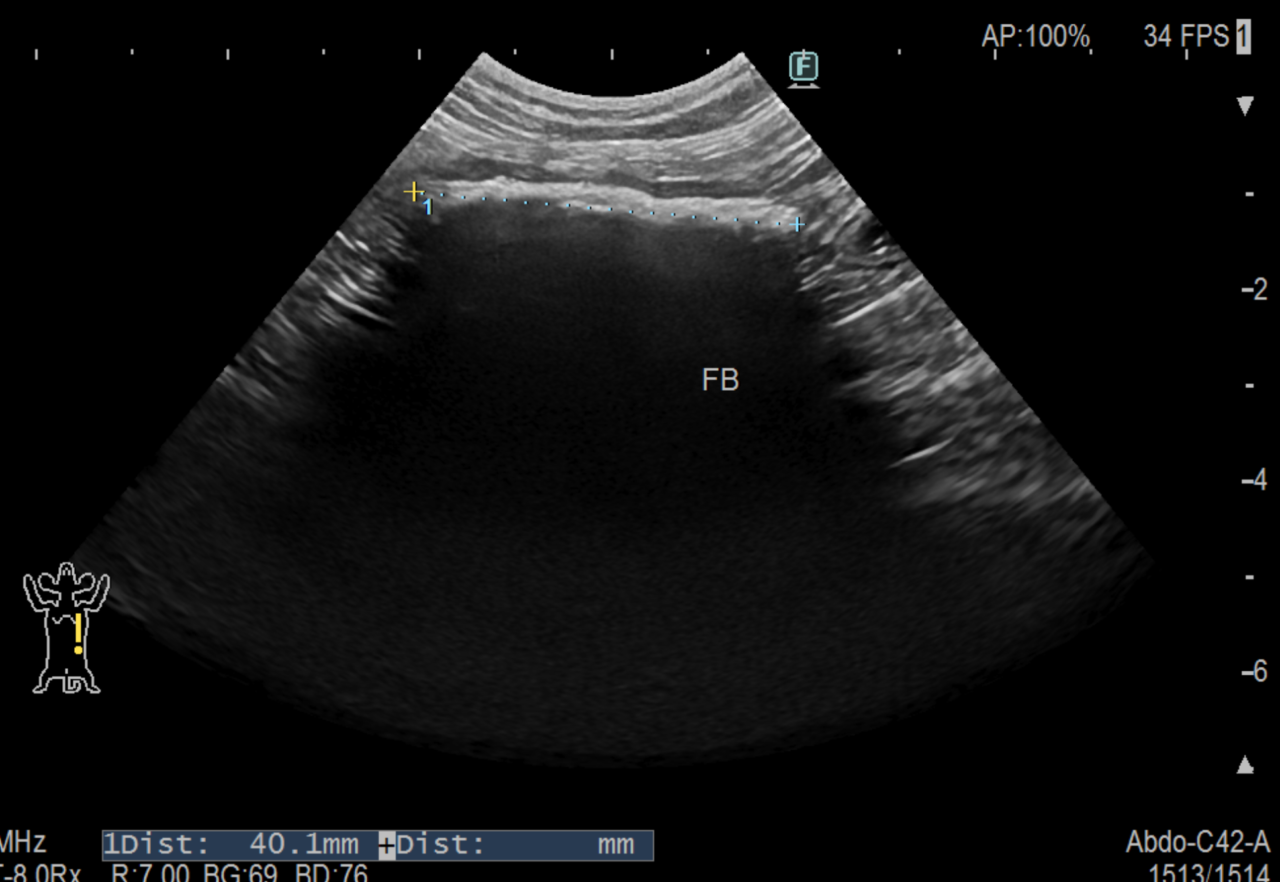

エコー検査では小腸に異物が完全閉塞していることが確認され、手術が必要と判断して当日中に腸切開手術を行いました。